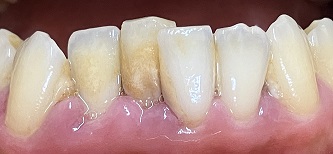

下画像2

歯肉の腫れ 初期むし歯あり(白濁)